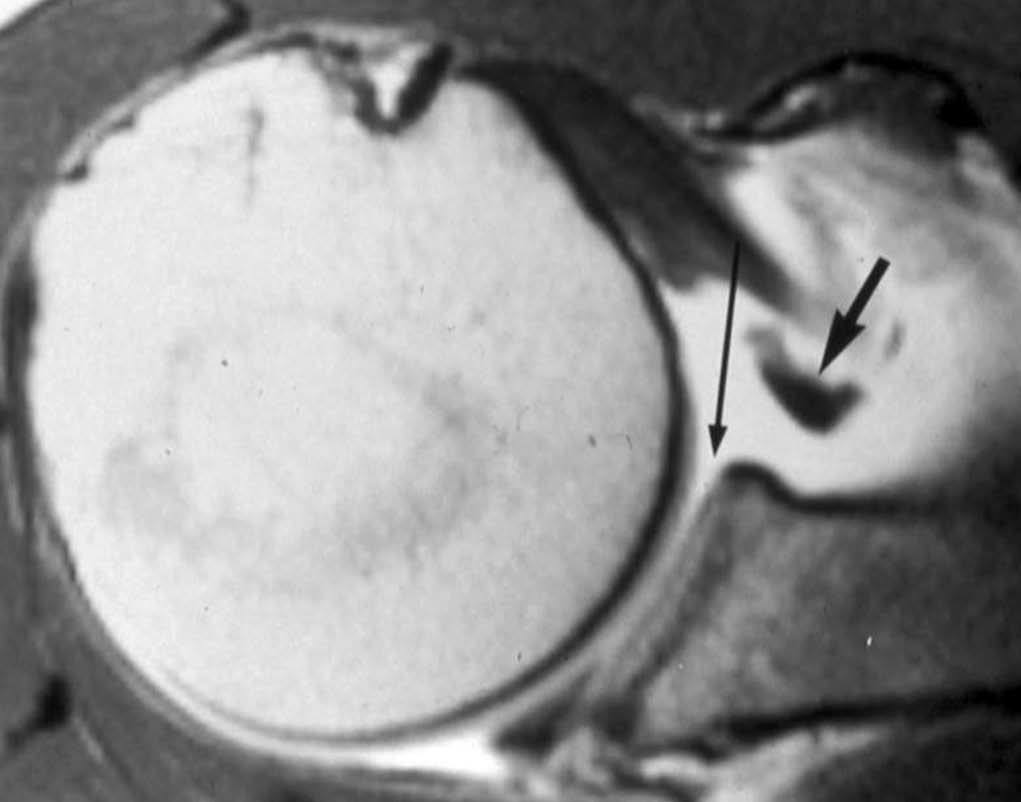

ALPSA (anterior labroliamentous periosteal avulsion)

Al igual que en el apartado anterior, existe también una separación de LG junto con la cápsula y el periostio, pero a diferencia de las lesiones de Bankart o Perthes, el LG se desplaza hacia dentro, por detrás del borde de la glenoides18 (fig. 12). La lesión de ALPSA puede cicatrizar por sinovialización (fig. 12), pero continúa siendo de carácter inestable.

Fig. 12.--ALPSA (anterior labroliamentous periosteal avulsion) agudo (A) y crónico (B). Nótese la separación del labio glenoideo y su desplazamiento posterior y medial por detrás del reborde glenoideo (flecha en A). En una fase crónica el labio glenoideo no se distingue como una estructura separada, sino como un engrosamiento de la unión entre el labio, la cápsula y el periostio (flecha en B).